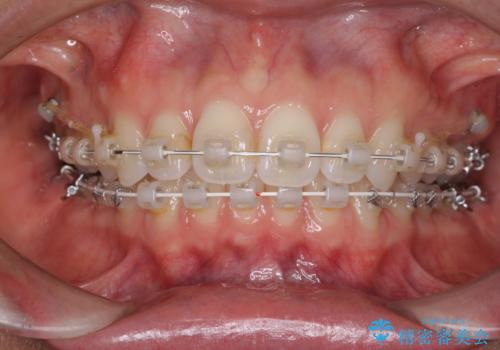

- 矯正装置

- 審美装置

咬合力が強いため、アンカースクリューを使用し、ワイヤー装置にて矯正治療を行うこととしました。

上顎歯列を下顎に対して4mmほど移動させる必要があったため、治療は長期化することが予想されましたが、患者様にはこちらの期待以上にゴムかけなどに協力いただき、補綴治療も含めて2年強で終えることができました。